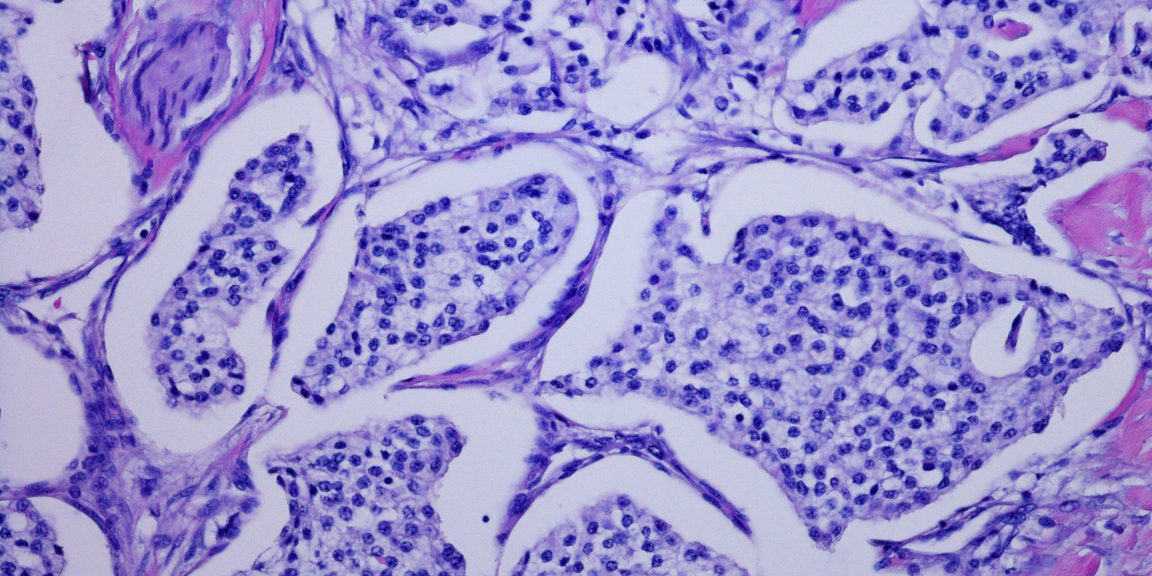

Jonathan Olivier (JO) : Le premier axe de recherche est clinique et se concentre sur le rôle de l’IRM et des biopsies pour diagnostiquer et classer l’agressivité des cancers de la prostate. Le second, mené au laboratoire Hétérogénéité, Plasticité et Résistance aux Thérapies des Cancers (CANTHER) d’ONCOLille, est plus fondamental et étudie les mécanismes par lesquels les adénocarcinomes de la prostate se transforment en tumeurs neuroendocrines pour devenir résistants aux traitements.

JO : Une tumeur neuroendocrine est une forme agressive de cancer de la prostate qui se développe lorsque des adénocarcinomes (cancers des glandes) se transforment sous l’effet de traitements comme l’hormonothérapie. Cette transformation est un mécanisme de résistance au traitement.

JO : Alors que les adénocarcinomes prostatiques sont principalement métastatiques au niveau des os, les tumeurs neuroendocrines envahissent préférentiellement les viscères. Elles peuvent se propager au foie, aux poumons et au cerveau, bien que le mécanisme de ce changement de cible ne soit pas encore bien compris.

JO : Les trois objectifs principaux sont de comprendre le mécanisme de transformation de l’adénocarcinome en tumeur neuroendocrine, de trouver un nouveau marqueur pour détecter cette transformation, et enfin d’identifier des cibles de traitement pour pouvoir proposer une thérapie adaptée une fois la transformation identifiée.